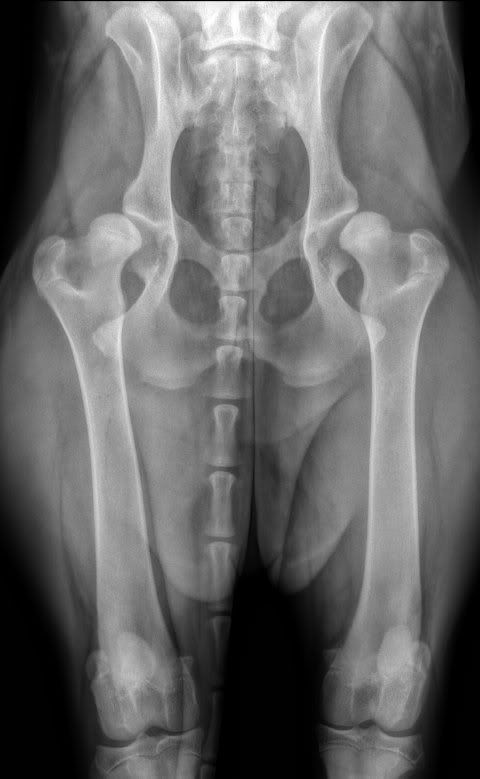

Dan een ander geval: een Sint Bernard teef van ruim 7 maanden oud. Ook binnengebracht wegens manken.

Dit zijn schokkend slechte heupen. Beide heupkoppen liggen half uit de kom. Ook hier kan geen definitieve kwalificatie gegeven worden omdat de teef nog te jong is maar dit zijn en blijven waardeloze heupen. Een D of een E zal het hoogst haalbare zijn op de leeftijd van 18 maanden.